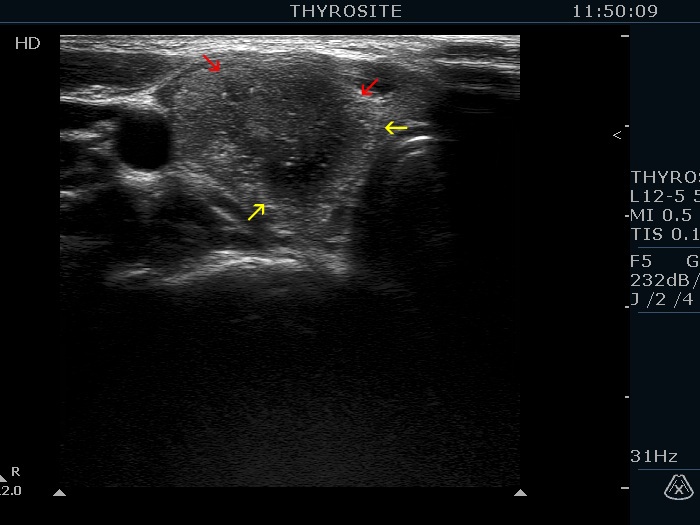

The borders of the nodule - case 2082 (ultrasonographic picture 1b)

Right lobe, another transverse scan. The lesion presents blurred, spiculated and lobulated margins, too. Yellow arrows point to lobulations while red do to spiculations.